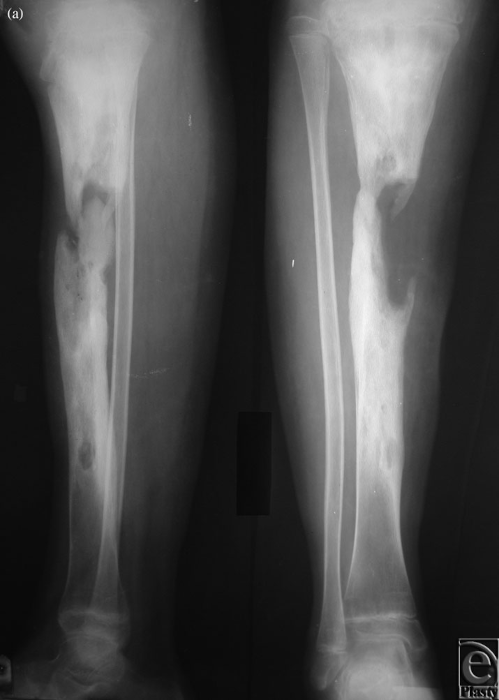

Osteomielite

- Descrizione: Infezione dell'osso e del Midollo osseo causata da Batteri, Micobatteri o Funghi.